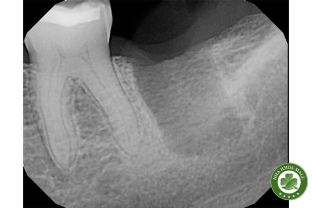

Trong thực hành nha khoa, không hiếm gặp những bệnh nhân than phiền đau tại vùng đã nhổ răng từ lâu, mặc dù niêm mạc bề mặt hoàn toàn bình thường và không có dấu hiệu viêm nhiễm. Khi chụp phim X-quang, bác sĩ có thể phát hiện đường viền mờ của một ổ răng cũ – dấu hiệu đặc trưng của ổ chân răng sót lại (residual root socket).